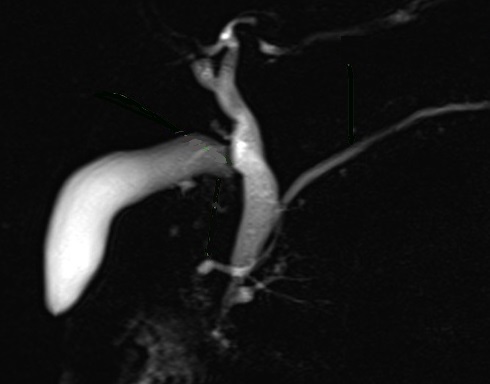

Image radiologique cholangio-wirsungo-IRM normal des

canaux pancreatiques ,de la vesicule biliaire et des

voies biliaires principale |

Image radiologique CPRM d'une pancreas

divisum de type I . Le canal pancreatique principale

est s'aboucher pans la papille mineur duodenum , le

canal ventral etre en jonction avec voie

biliaire principale et s'abouche au papille

majeur |